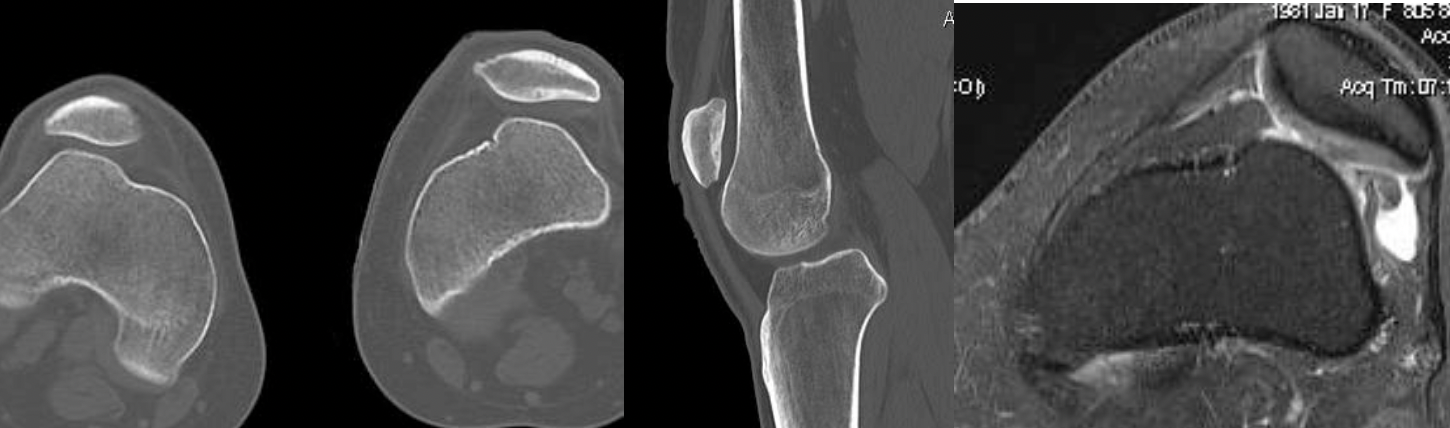

1. Isolated Patella tilt

Indications

- clinical and xray patella tilt

- no instability / malalignment

- excessive lateral pressure syndrome

5. Trochlea dysplasia

- trochleoplasty

Trochleoplasty

Indication

- trochlea dysplasia

- if after MPFL and TTT the patella still unstable at end of case